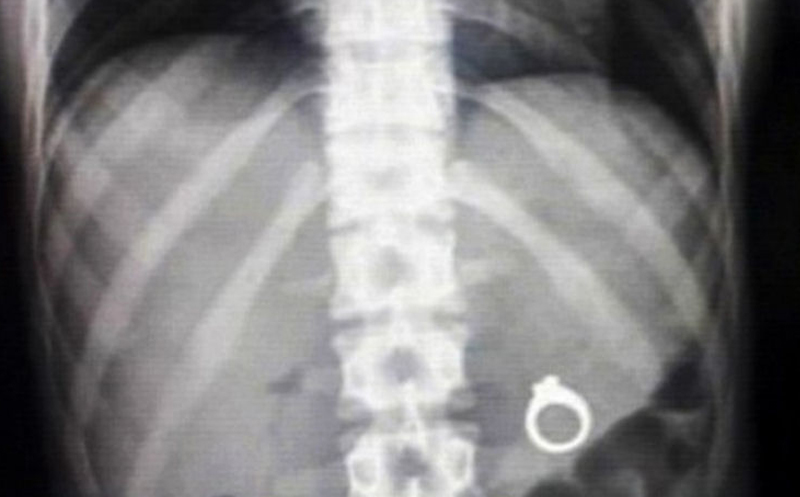

Обручальное кольцо

Когда хотите оригинально сделать предложение возлюбленной, главное — просчитать возможные неприятные варианты. Рид Харрис спрятал обручальное кольцо в мороженое, а его девушка Кейтлин так увлечённо ела любимое лакомство, что проглотила колечко. Ирония в том, что она мало того, что не заметила этого, так ещё и не поверила Риду, когда он рассказал о своей задумке. Парню пришлось срочно везти её на рентген, чтобы доказать свою изобретательность и вызволить ювелирный символ любви.